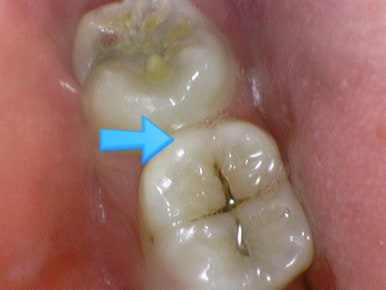

충치 제거 전- 충치제거 중간에 찍은 사진/ 눈에 안보이던 충치가 더 깊은 것을 볼 수 있음

엑스레이로 인레이를 해야함을 진단받고

겉에 보이는 충치와 엑스레이 상의 충치부위를 파보면

엑스레이로 예상했듯이

위의 좌우사진처럼 겉에서는 하얗게 보이는 부위가 오히려 더 깊은 충치가 있음을 볼 수 있었습니다.